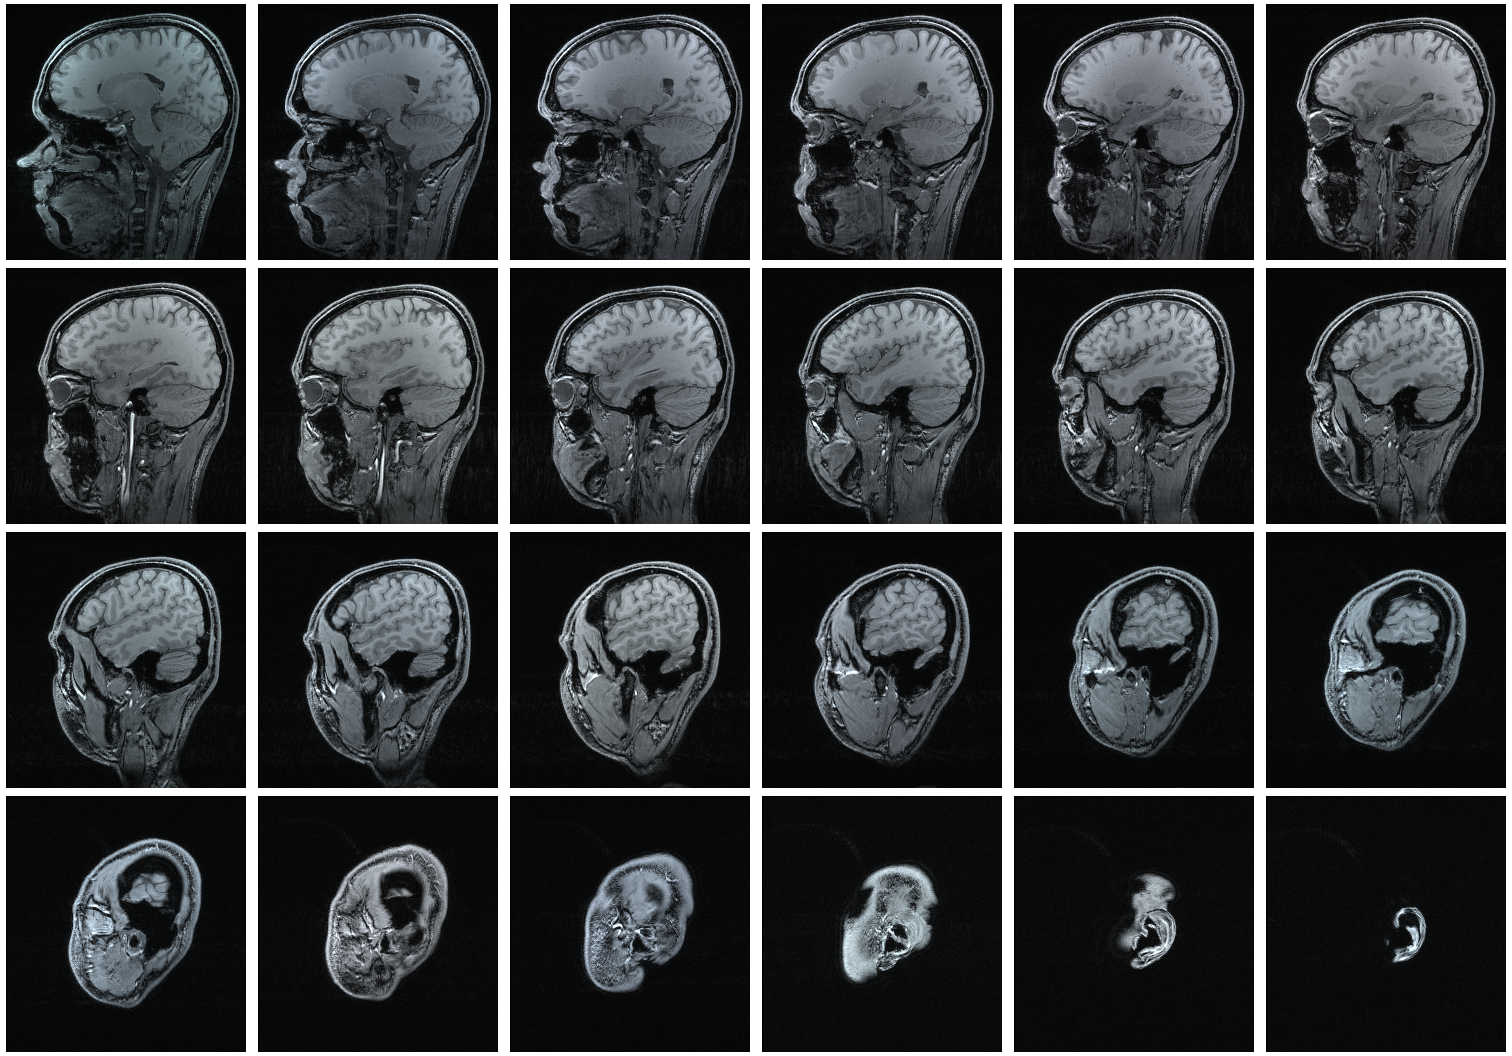

Hasil pemeriksaan MRI adalah berupa rekaman citra potongan penampang tubuh/organ manusia dengan menggunakan medan magnet berkekuatan antara 0,064 – 1,5 Tesla dan resonansi getaran terhadap inti atom hidrogen. Contoh citra kepala hasil pemeriksaan dengan modalitas MRI ditunjukkan pada gambar di bawah ini.

Citra MRI dalam matlab terdiri dari 27 slice tampang horizontal (axial). Tampang horizontal tersebut kemudian ditransformasi menjadi tampang sagittal (35 slice) dan tampang coronal (45 slice) menggunakan transformasi radon. Selanjutnya masing-masing tampang divisualisasikan secara tiga dimensi.